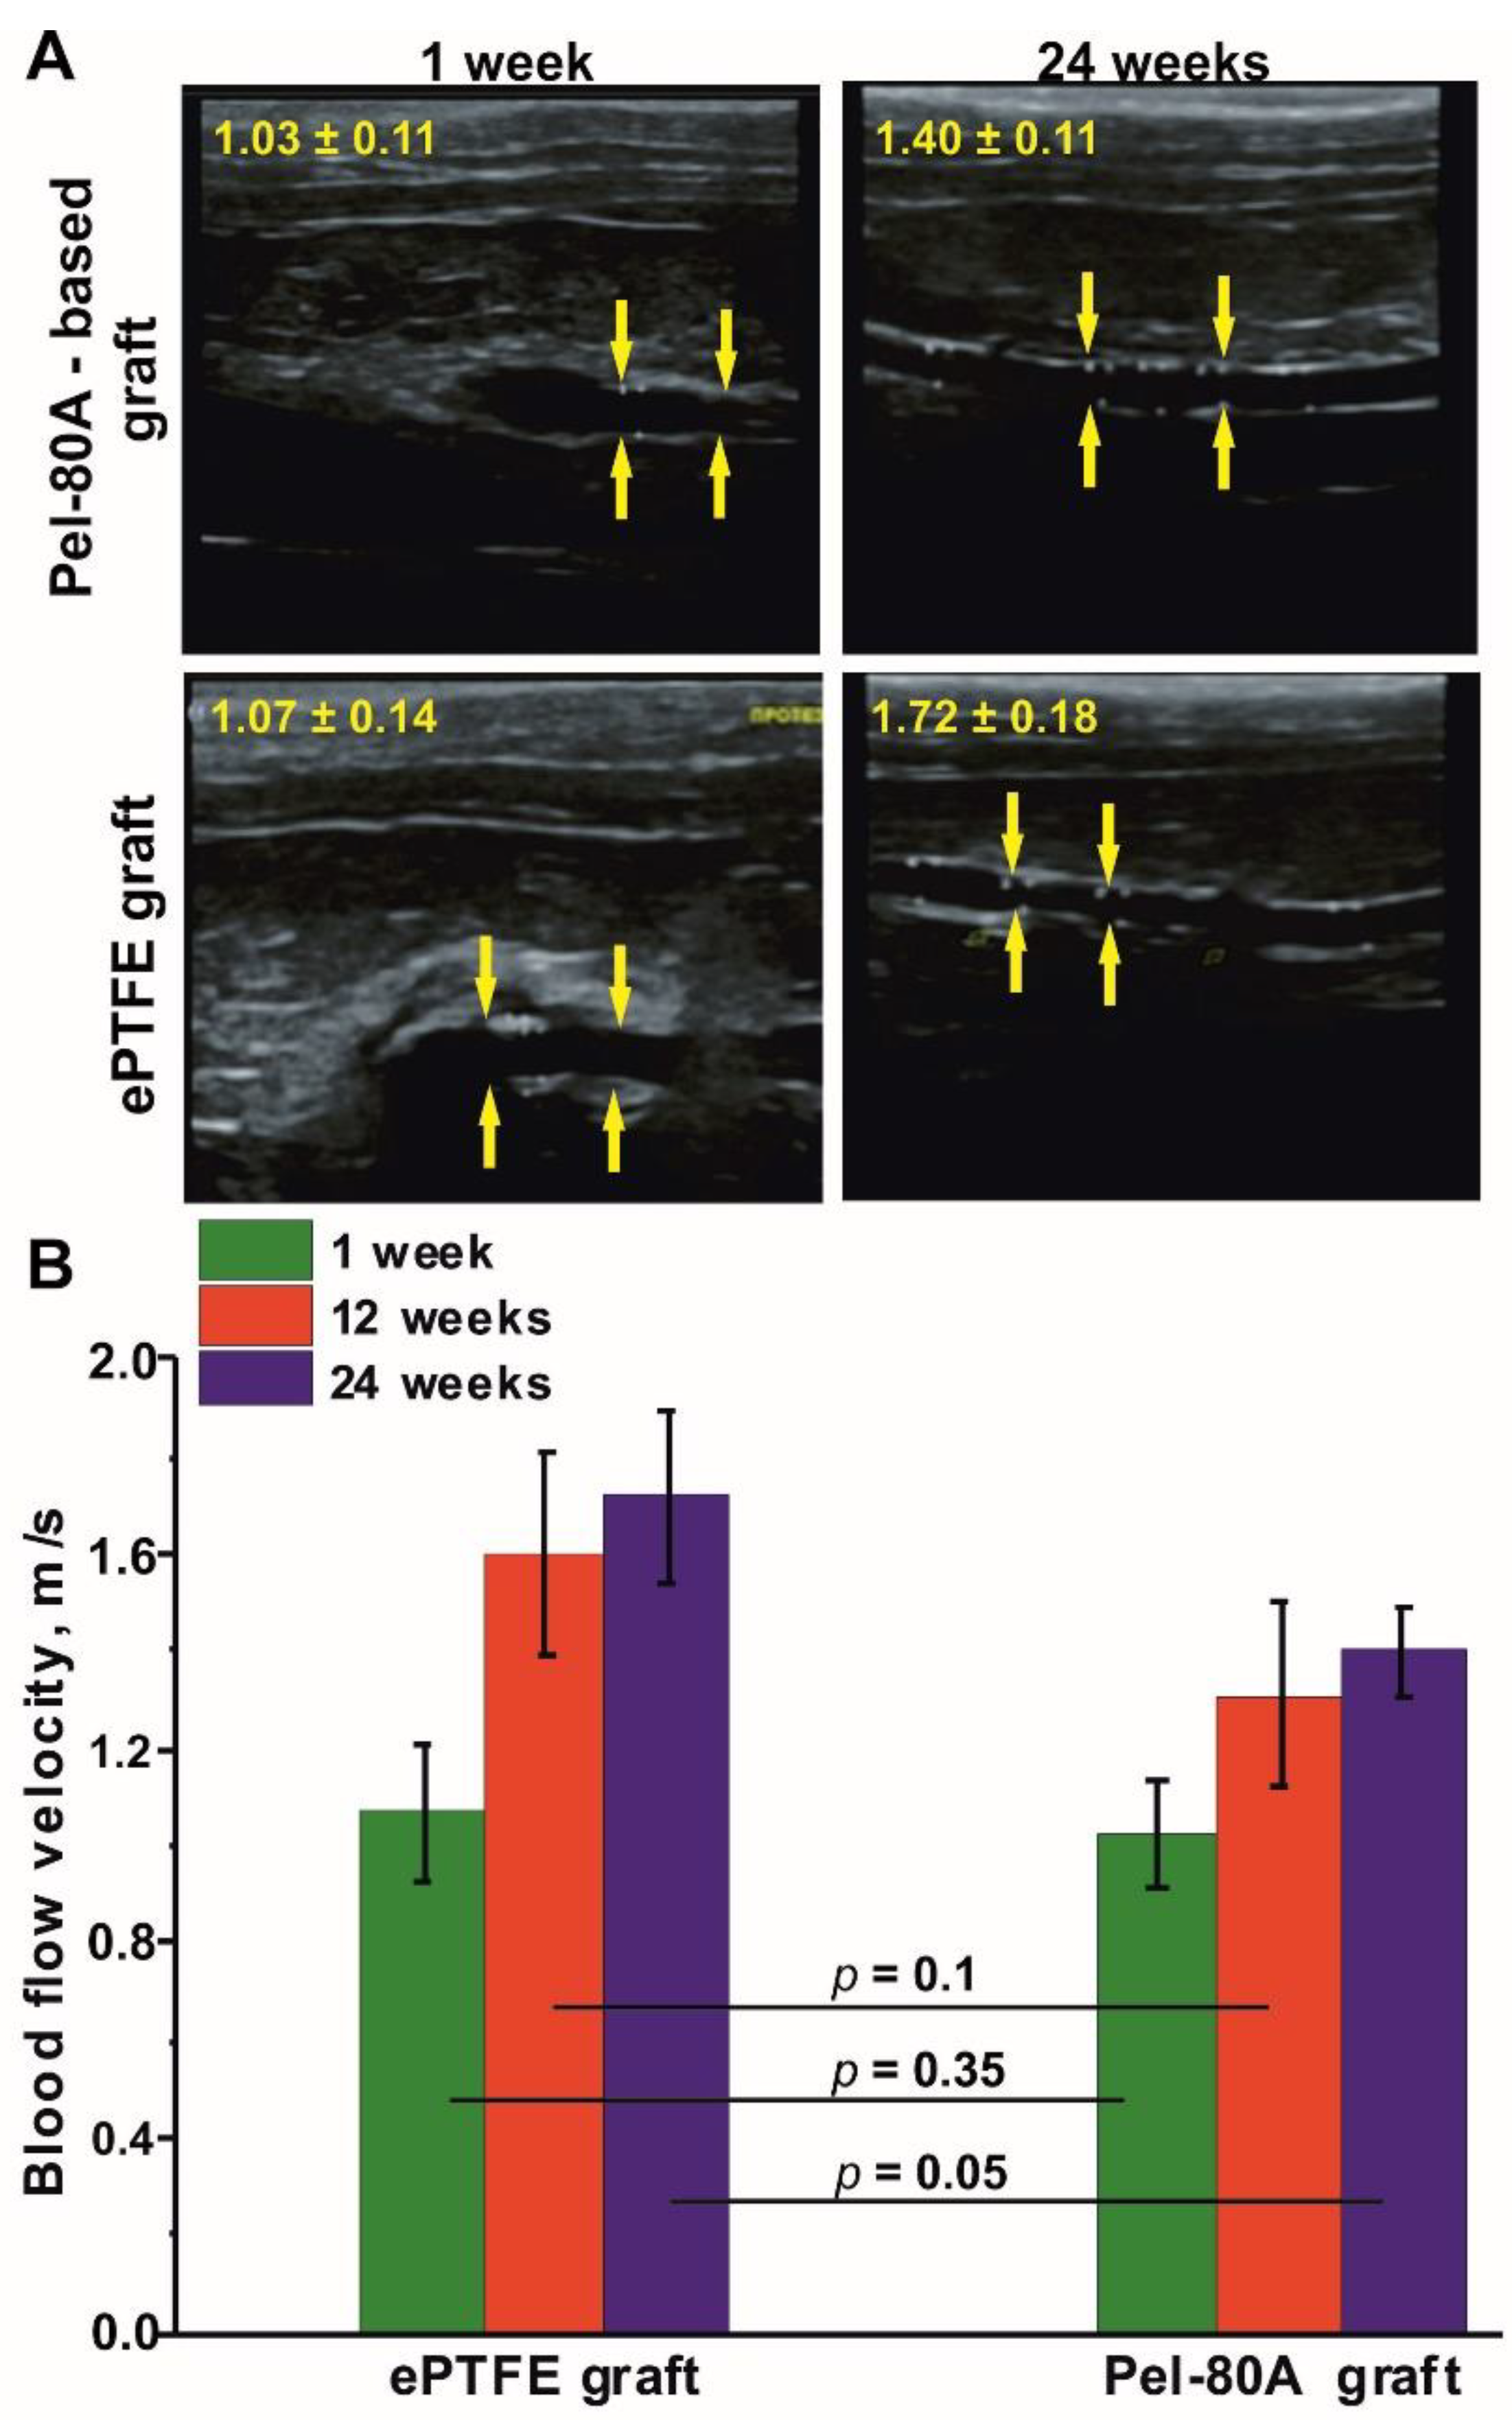

3.3. In Vivo Study of Pel-80A-Based SDVGs